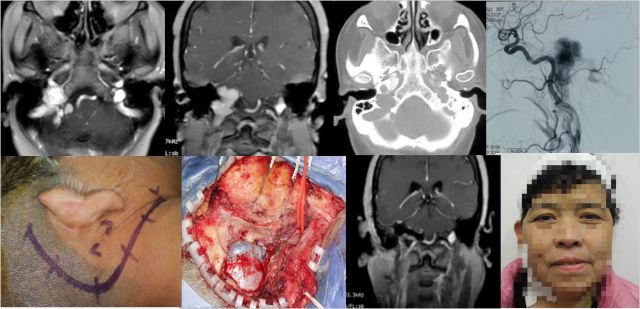

颈静脉孔内外沟通型神经鞘瘤

内镜经口+乙状窦后入路显微手术 分期手术

幕上下联合入路

颈静脉球瘤